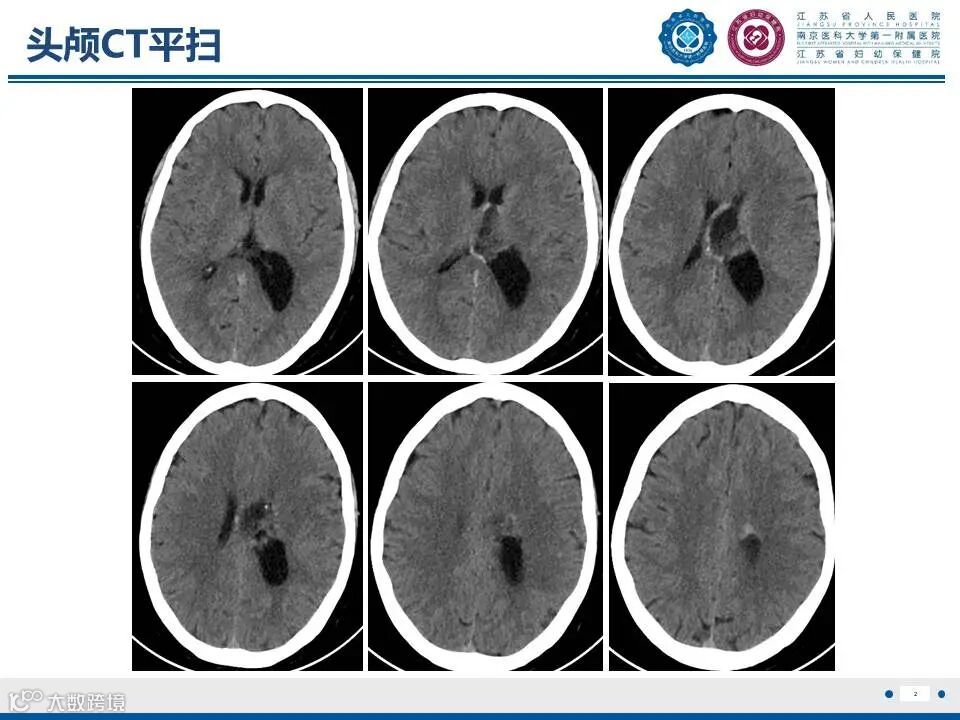

来源:江苏省人民医院放射科